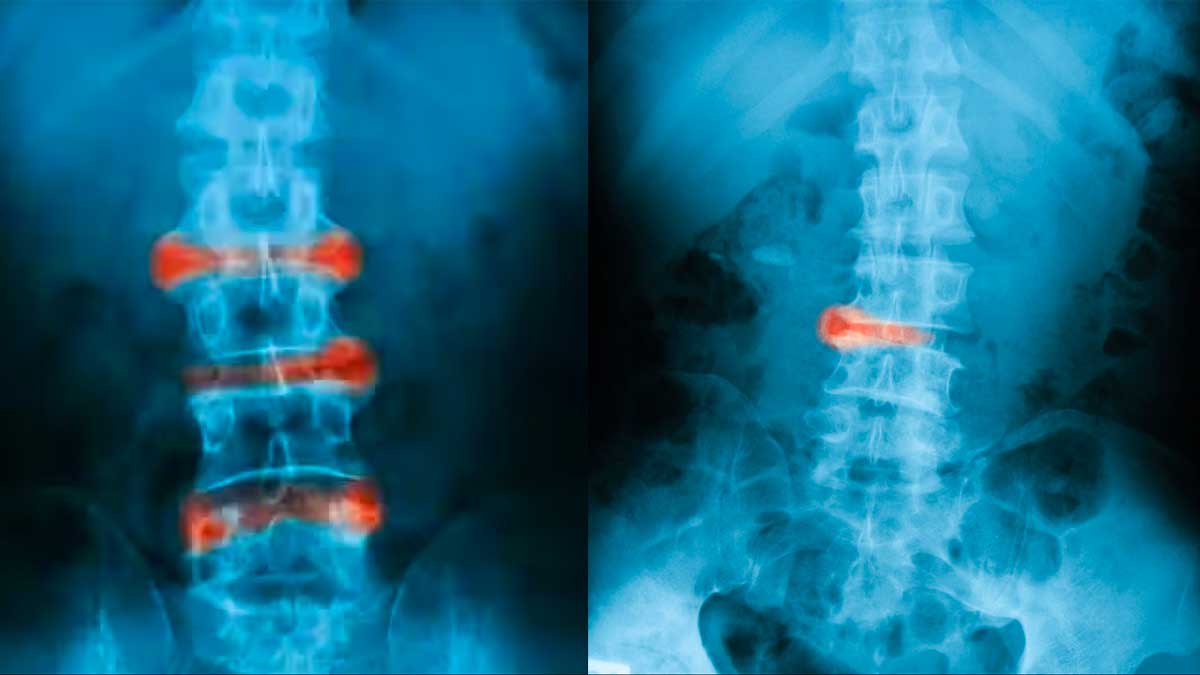

According to an overview published by the National Institute of Arthritis And Musculoskeletal and Skin Diseases, 'Ankylosing spondylitis is a type of arthritis that causes inflammation in the joints and ligaments of the spine.'

This autoimmune condition often begins with lower back pain and stiffness, gradually progressing to involve the entire spine. Morning stiffness is a hallmark, and over time, individuals may experience reduced flexibility and mobility.

Even diagnosing Ankylosing Spondylosis is challenging, as its symptoms overlap with other conditions.